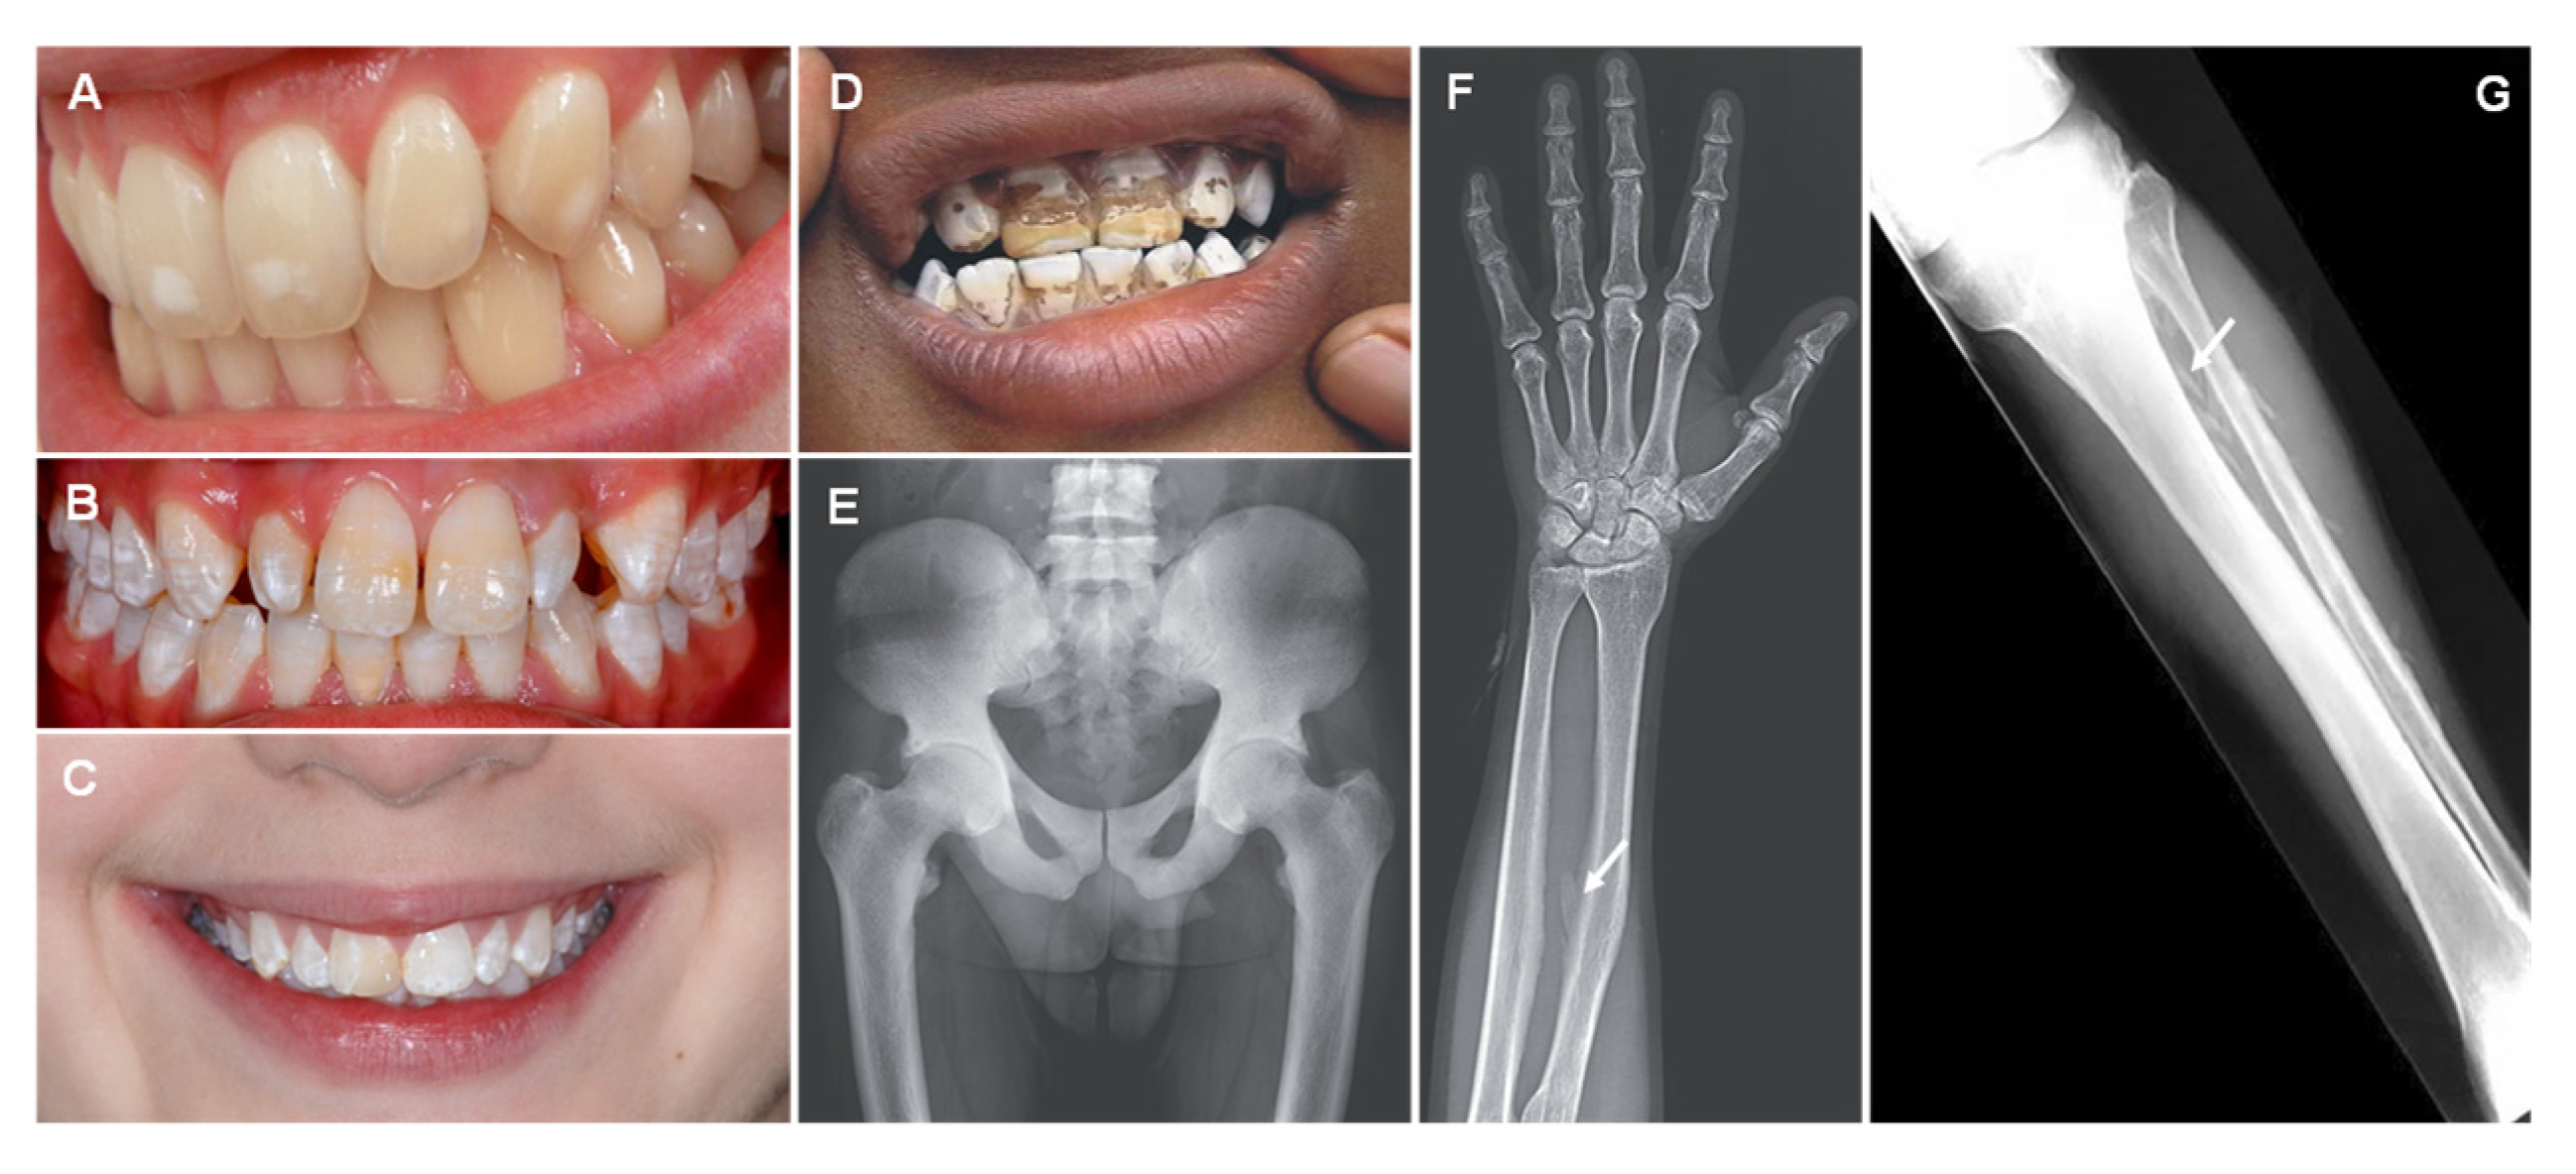

6. Fluorine

| Fluorine (F) |

| Dental fluorosis Skeletal fluorosis: diffuse bone condensation and interosseous membrane calcification, osteosclerosis and osteoporosis. |